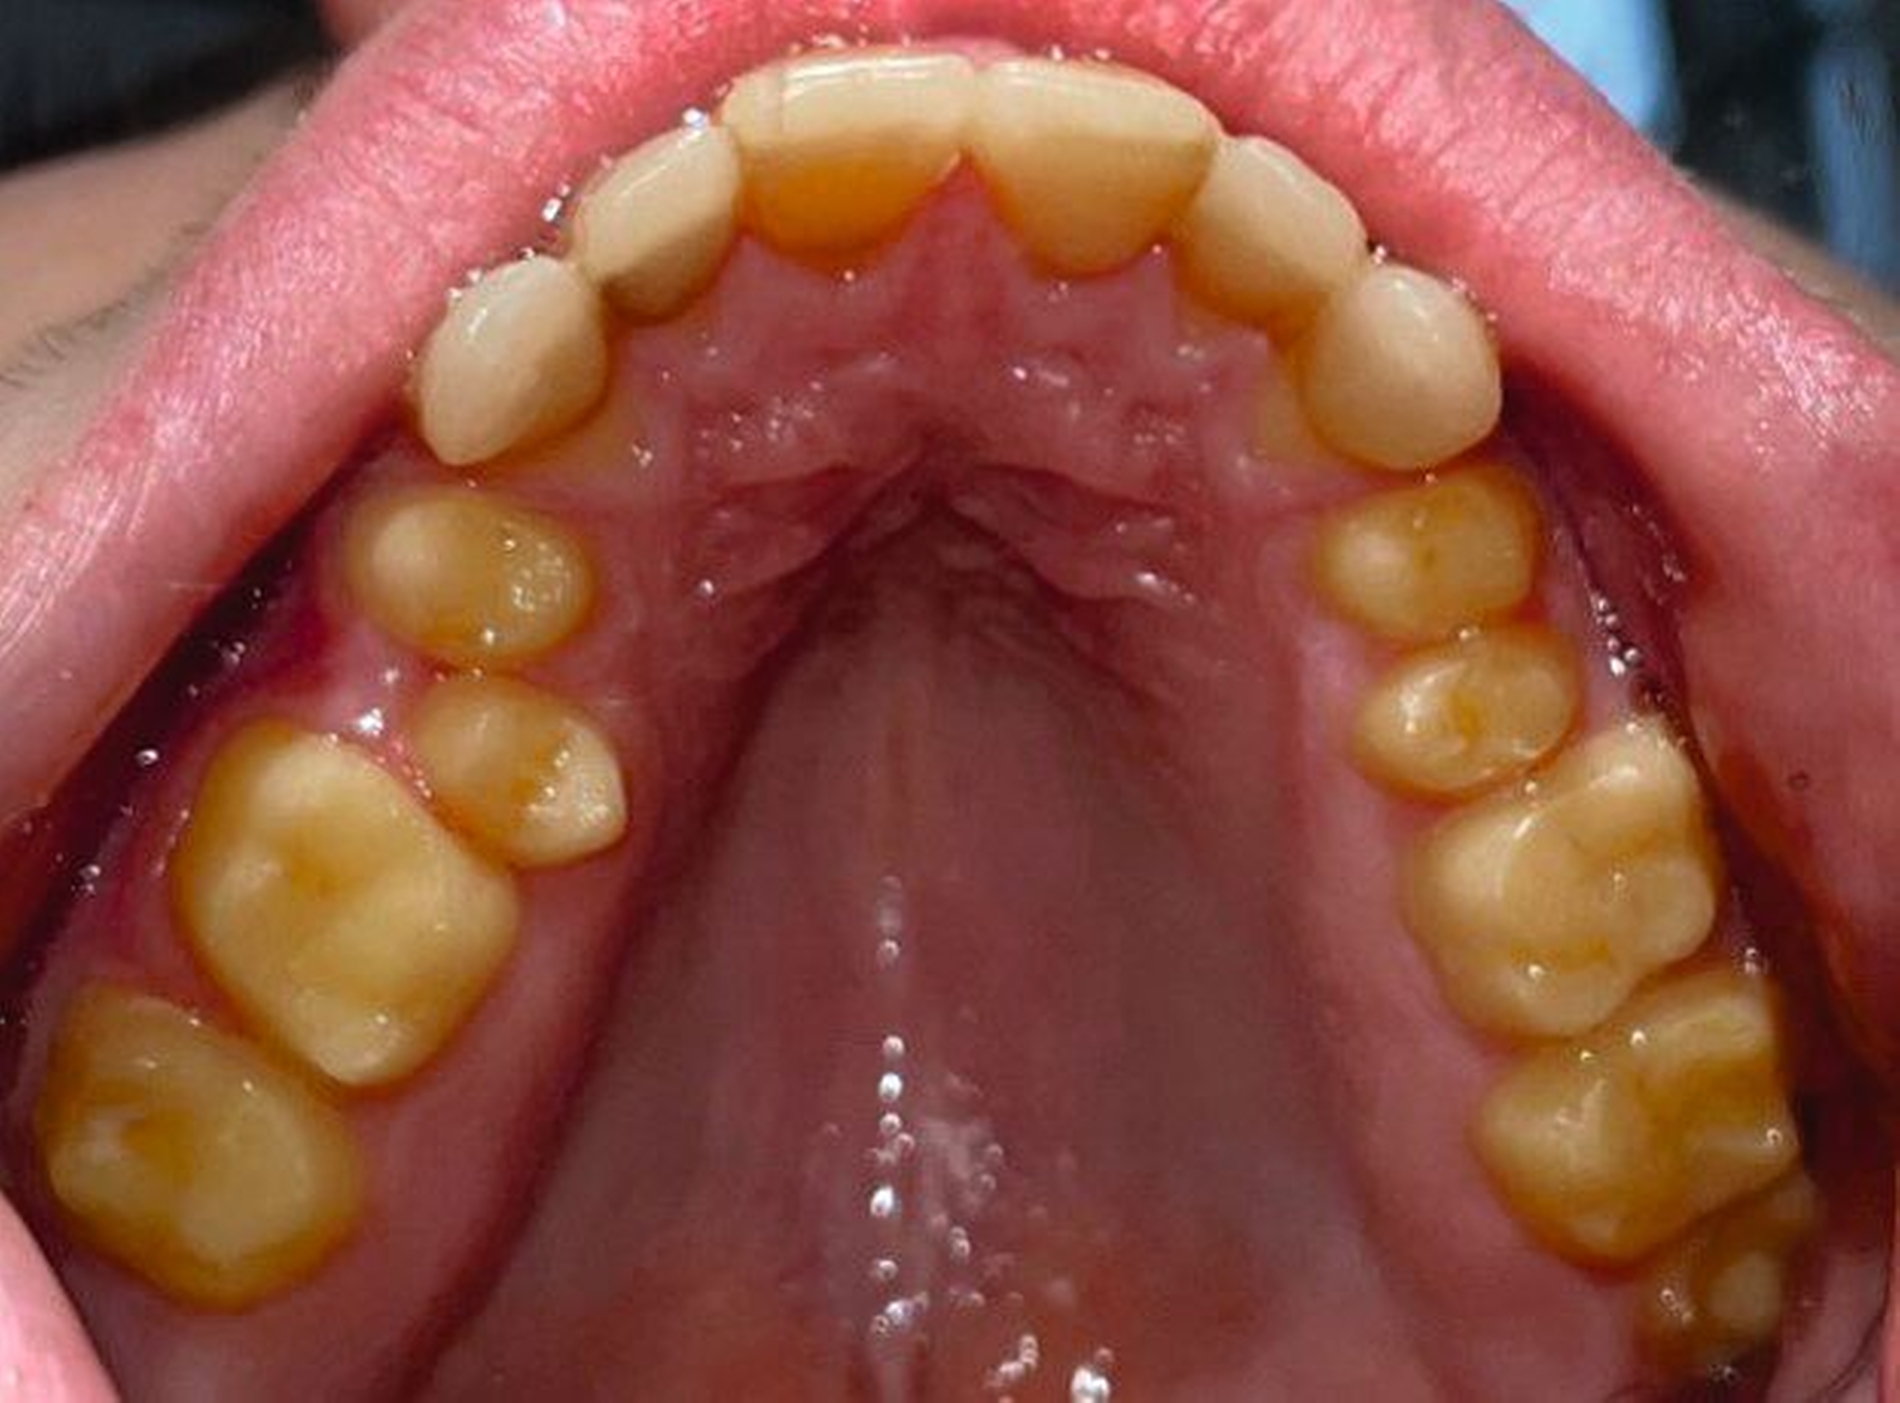

Klinisch zeigte sich ein kariöses Wechselgebiss mit generalisierten Verfärbungen und rauer Schmelzoberfläche. Mehrere Milch- und bleibende Zähne wiesen aktive kariöse Läsionen auf. Zahn 64 war zusätzlich druckdolent und gelockert, mit einer vestibulären Schwellung der Gingiva. Zudem bestanden eine Mittellinienabweichung, ein Overbite von vier Millimetern und ein Overjet von elf Millimetern (Abbildung 1). Extraoral fiel ein fliehendes Kinn mit inkomplettem Lippenschluss und hyperaktivem Musculus mentalis auf. Röntgenologisch waren alle Zähne angelegt, der Zahnschmelz zeigte jedoch eine reduzierte Opazität (Abbildung 2). Eine genetische Abklärung wurde von den Erziehungsberechtigten aus ethischen Gründen abgelehnt.

Klinisch zeigten sich ein nicht-kariöses Wechselgebiss mit generalisierter Schmelzhypoplasie an allen Zähnen sowie eine insuffiziente Mundhygiene. Zusätzlich bestanden eine fehlende Mittellinienübereinstimmung, ein Overbite von minus vier Millimetern und ein Overjet von sechs Millimetern (Abbildung 5), die sich phonetisch in einem interdentalen Sigmatismus äußerten. Röntgenologisch waren alle Zähne angelegt, jedoch war der Zahnschmelz stark reduziert oder vollständig fehlend (Abbildung 6).